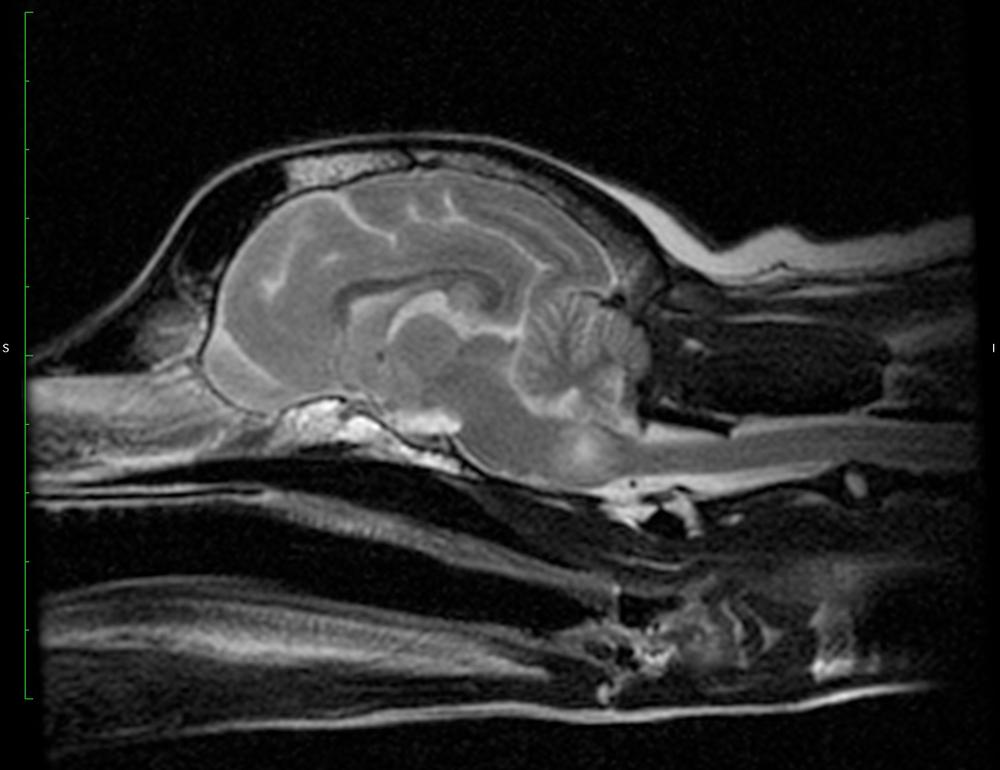

ЦНС

Этот тип изучен хуже всего. При поражении ЦНС животное может бесцельно кружиться на одном месте, раскачиваться при ходьбе или терять ориентацию в пространстве. В данном случае к основным симптомам относятся судороги, припадки и паралич.